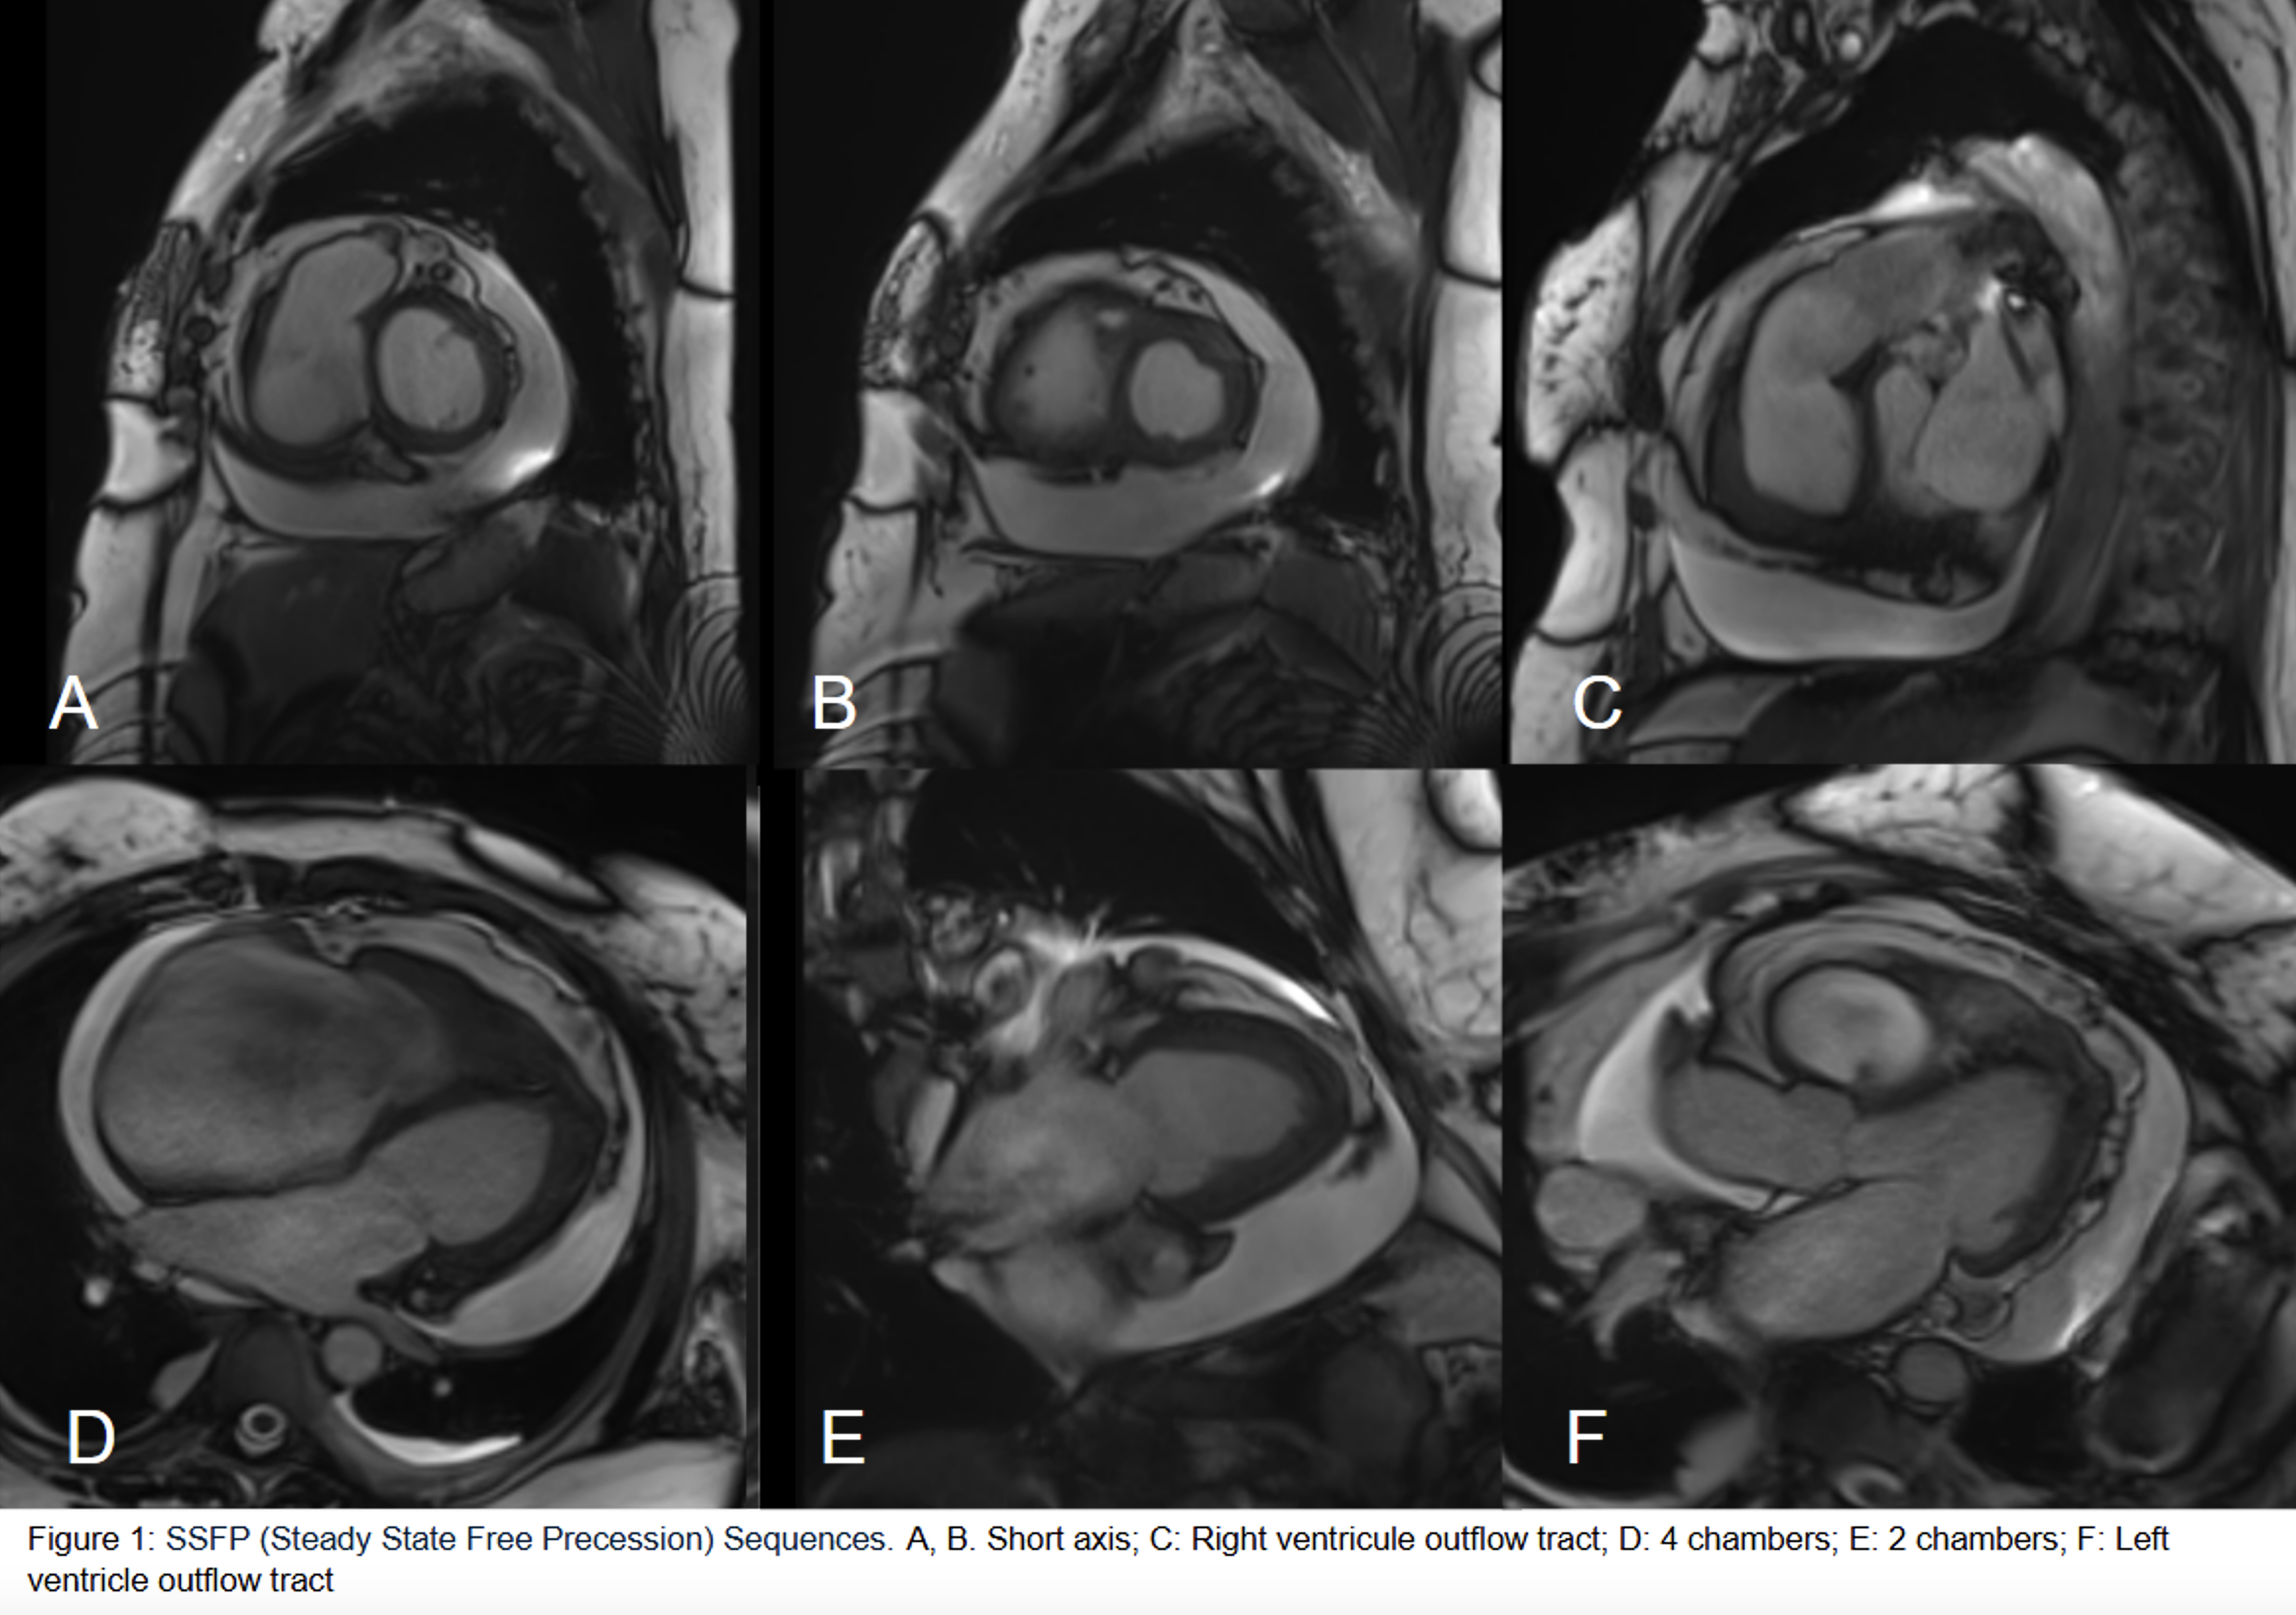

Late Gadolinium Enhancement sequences